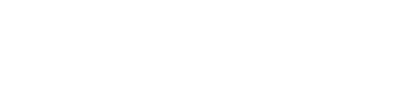

慢性甲状腺炎(橋本病)

慢性甲状腺炎(橋本病)甲状腺の表面がデコボコしています。

甲状腺全体が腫れて大きくなります。

甲状腺の内部が黒っぽくなり(エコーレベル低下)、むらがあります(内部不均質)。

※軽症の場合は正常な甲状腺とほとんど変わらない場合もあります。